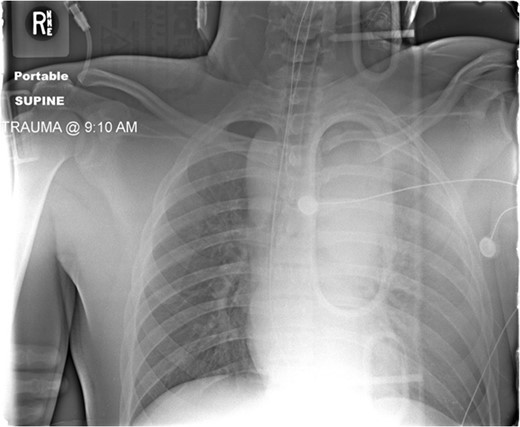

CXR following chest closure on postop day 3 demonstrated the aortic stent, multiple life support lines and bilateral lung opacification from the severe persistent respiratory failure.